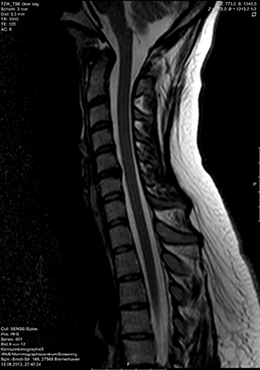

Die MRT ist hinsichtlich der Darstellbarkeit von verschiedenen Organen, Gefäßen, Bändern und Gelenken vielen anderen heute in der Radiologie zur Verfügung stehenden bildgebenden Verfahren überlegen. Insbesondere Entzündungsherde und vitale Tumoren können mit der MRT häufig besser erkannt werden als mit anderen Verfahren.

Im IRNB steht seit Beginn 2016 ein Magnetresonanztomograph der neuesten Gerätegeneration für Untersuchungen zur Verfügung, der sich durch eine verbesserte Bildqualität auszeichnet. Bei diesem Gerät ist auch der Röhrendurchmesser größer, so dass nicht nur für kräftige Patienten die Untersuchung komfortabler wird.